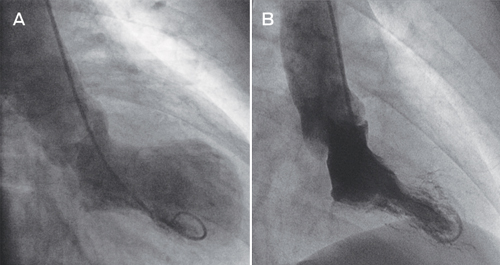

Selective coronary angiography revealed no significant coronary artery stenosis. Left ventriculography demonstrated left ventricular systolic dysfunction with severe hypokinesis and apical ballooning (Box, A). Transthoracic echocardiography confirmed the left ventriculography findings. There was no evidence of myocardial infarction on cardiac magnetic resonance imaging. We made a diagnosis of takotsubo cardiomyopathy.

The syndrome was first reported in the Japanese cardiology literature in 1991.2 It is named for the resemblance of left ventricle morphology on ventriculography during the acute phase to that of a Japanese octopus trap and is synonymous with the terms apical ballooning syndrome or ampulla cardiomyopathy. Since the initial description, at least two other accepted ballooning patterns (mid ventricular and basal) have been described.3